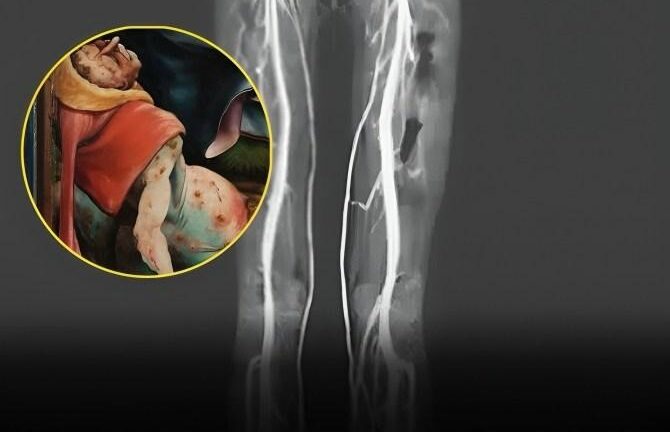

Woman Experiencing Burning Pains Turns Out To Have Medieval ‘Holy Fire’ Disease

After she had been feeling a severe burning sensation in her legs for two days, a 24-year-old woman went to an outpatient clinic. The feeling was traveling from her toes to the middle of her thighs. Her feet had begun to discolor, and she was having difficulty walking. The doctors who examined her noticed that […]